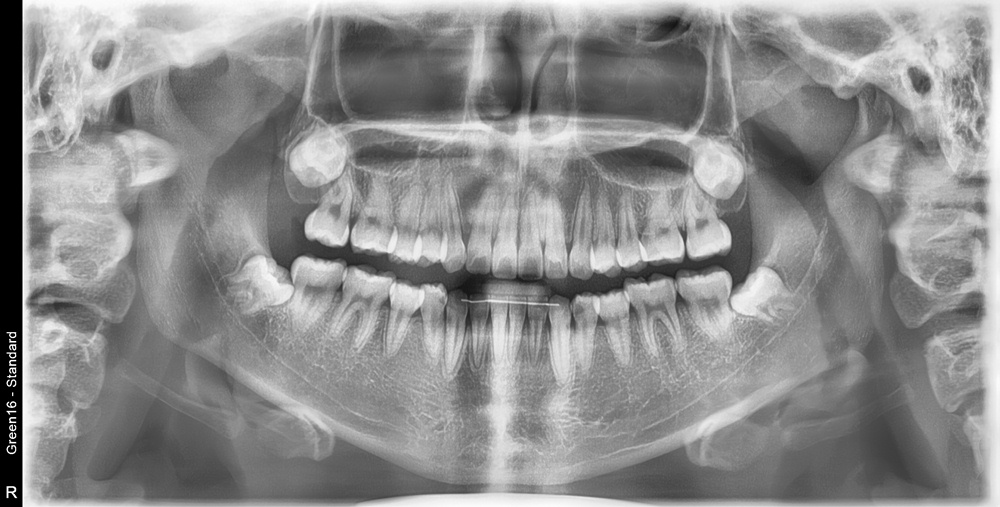

치료 전 사진입니다.